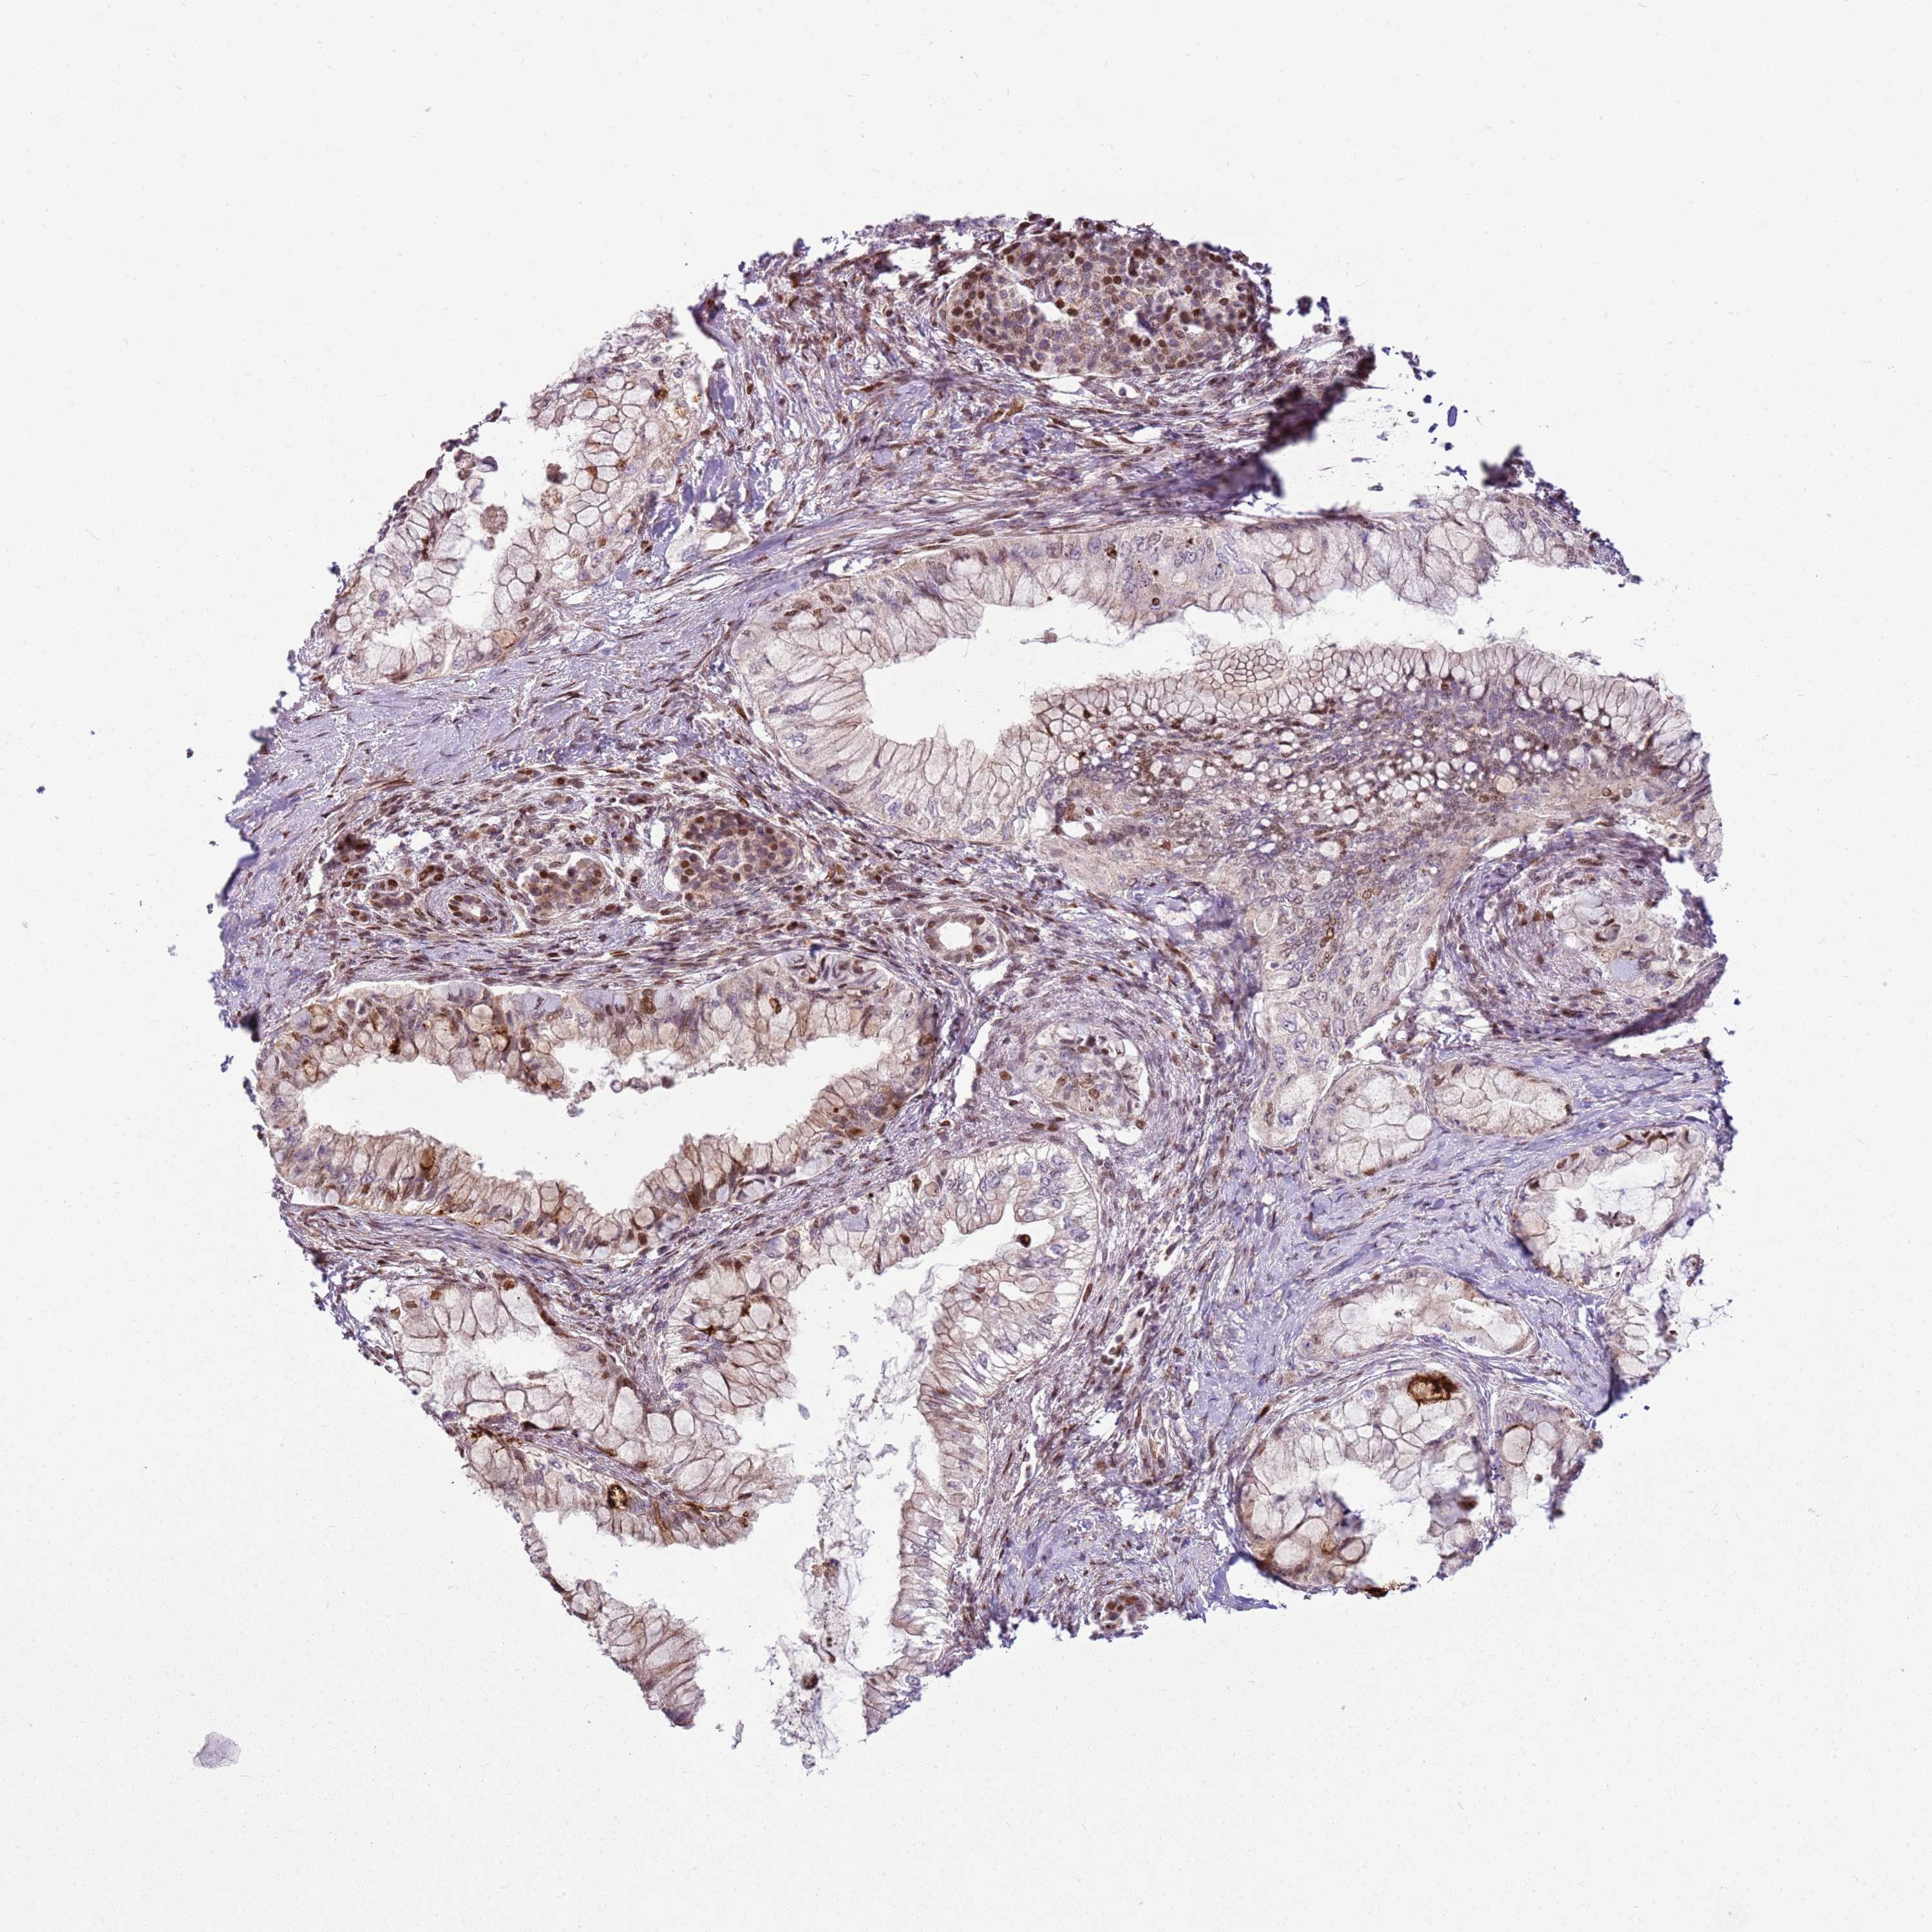

PANCREATIC CANCER - Protein expressioni

A mouse-over function shows sample information and annotation data. Click on an image to view it in a full screen mode. Samples can be filtered based on level of antibody staining by selecting one or several of the following categories: high, medium, low and not detected. The assay and annotation is described here.

Note that samples used for immunohistochemistry by the Human Protein Atlas do not correspond to samples in the TCGA dataset.

Antibody stainingi

Antibody staining in the annotated cell types in the current human tissue is reported as not detected, low, medium, or high, based on conventional immunohistochemistry profiling in selected tissues. This score is based on the combination of the staining intensity and fraction of stained cells.

Each image is clickable and will lead to virtual microscopy that enables deeper exploration of all samples and also displays staining intensity scores, fraction scores and subcellular localization as well as patient and tissue information for each sample.

Antibody HPA022979

Staining

High

Medium

Low

Not detected

Intensity

Strong

Moderate

Weak

Negative

Quantity

>75%

75%-25%

<25%

None

Location

Nuclear

Cytoplasmic/membranous

Cytoplasmic/membranous,nuclear

Adenocarcinoma, NOS